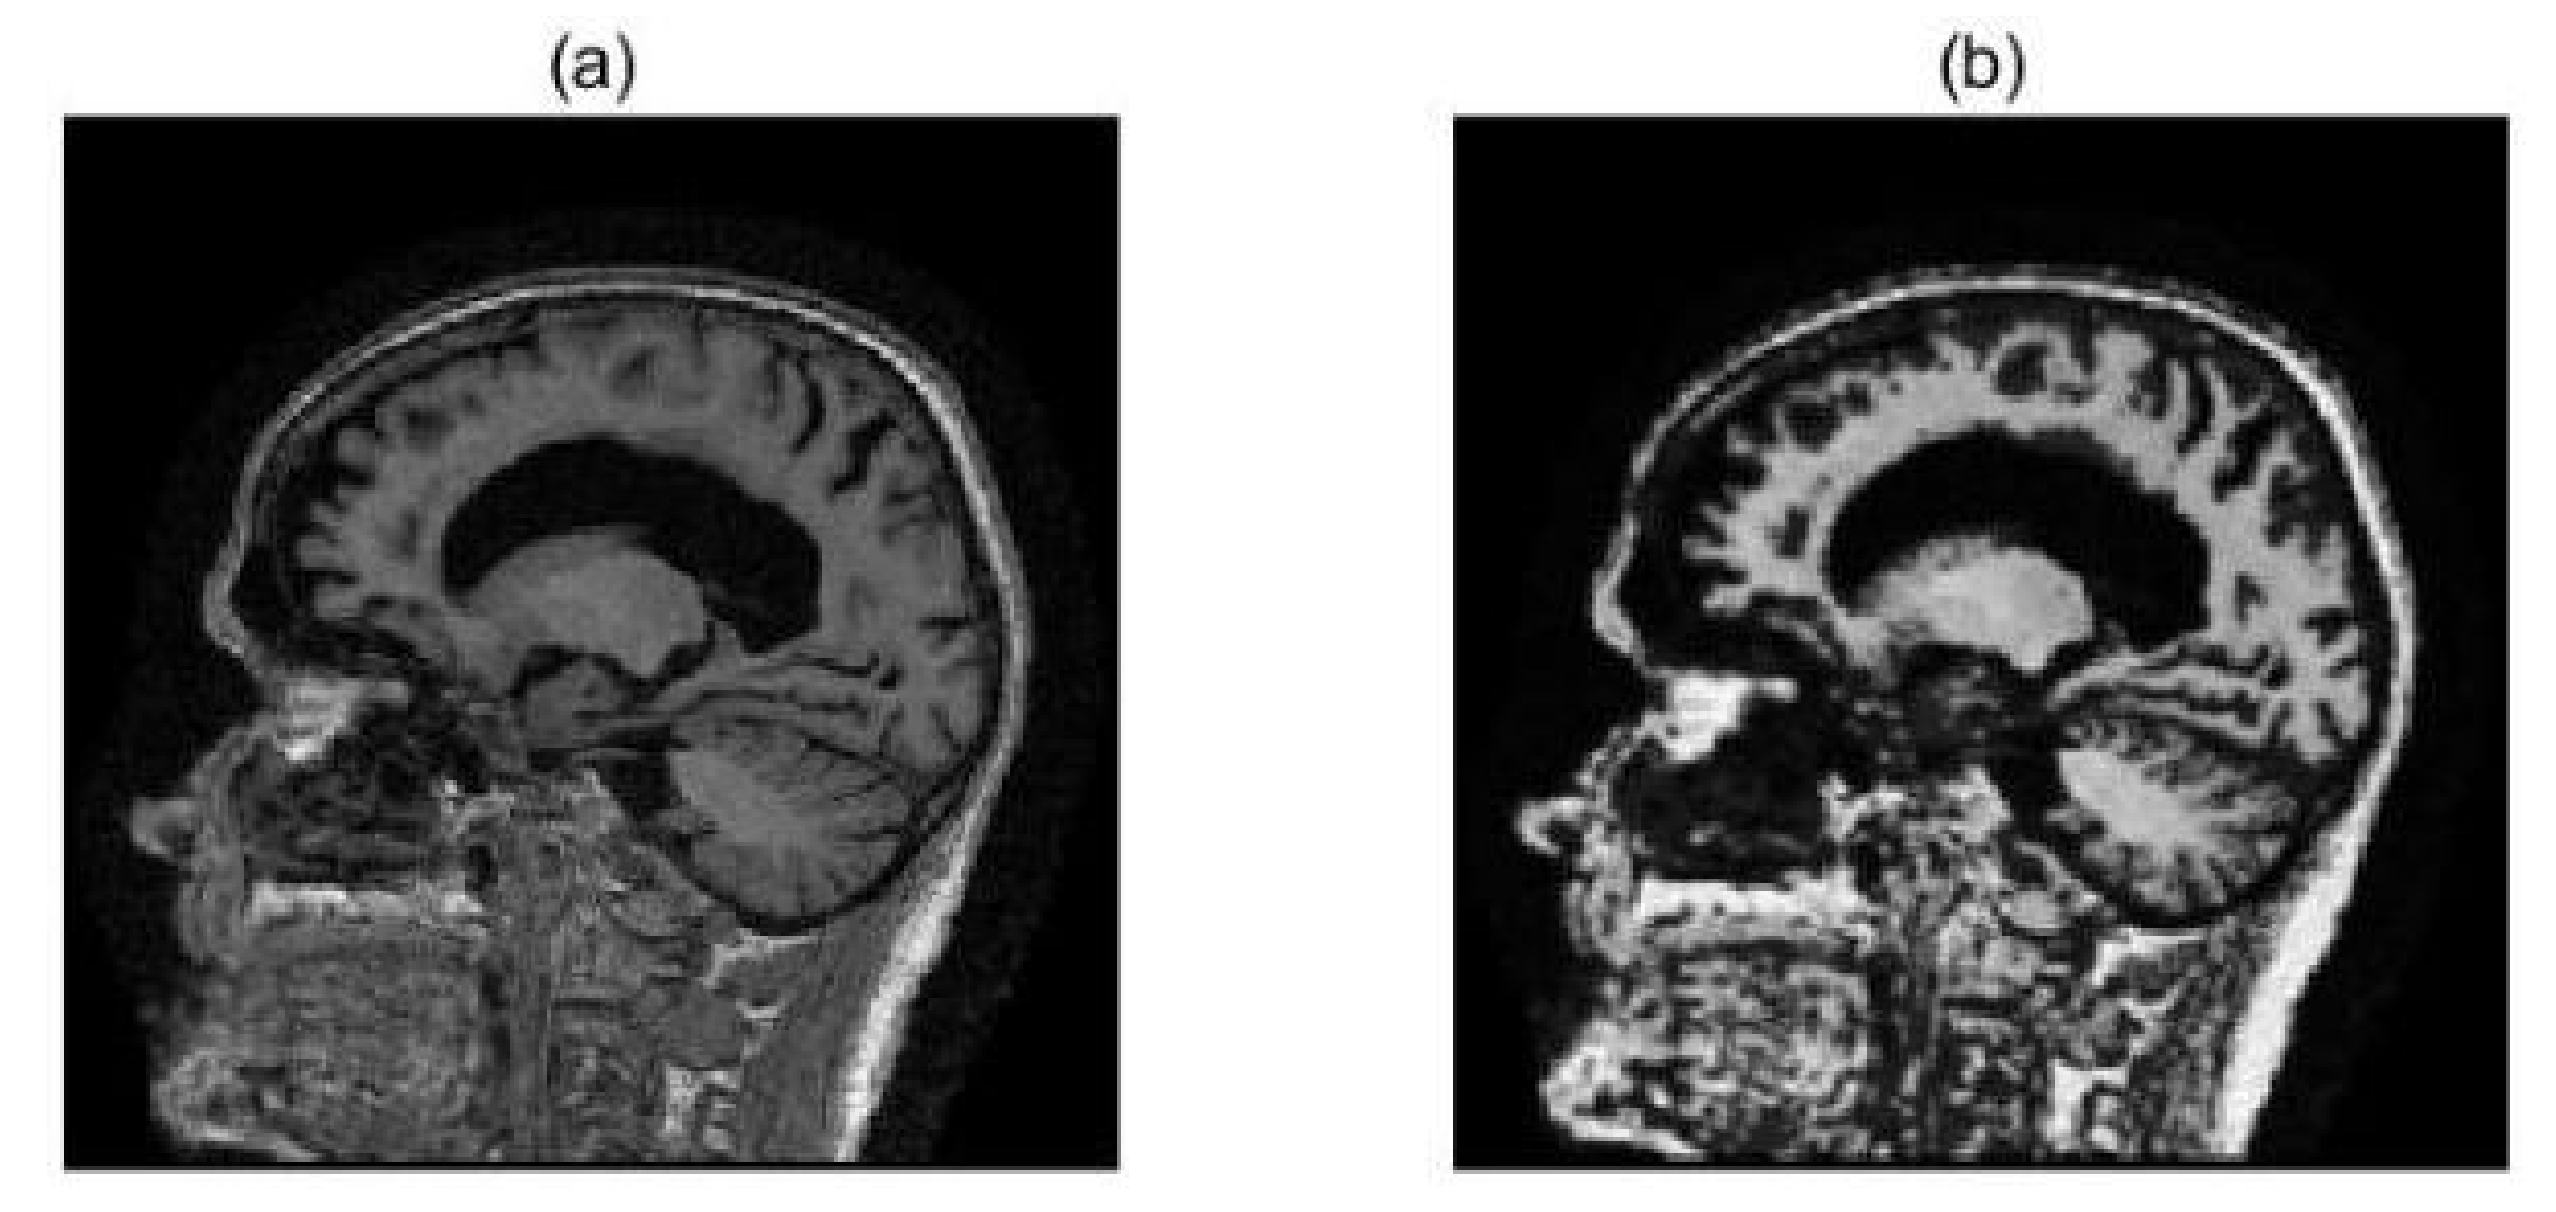

2.2. Image Preprocessing

3.1. Multimodal Image Fusion Results

3.2. Evaluation and Analysis of Fused Images